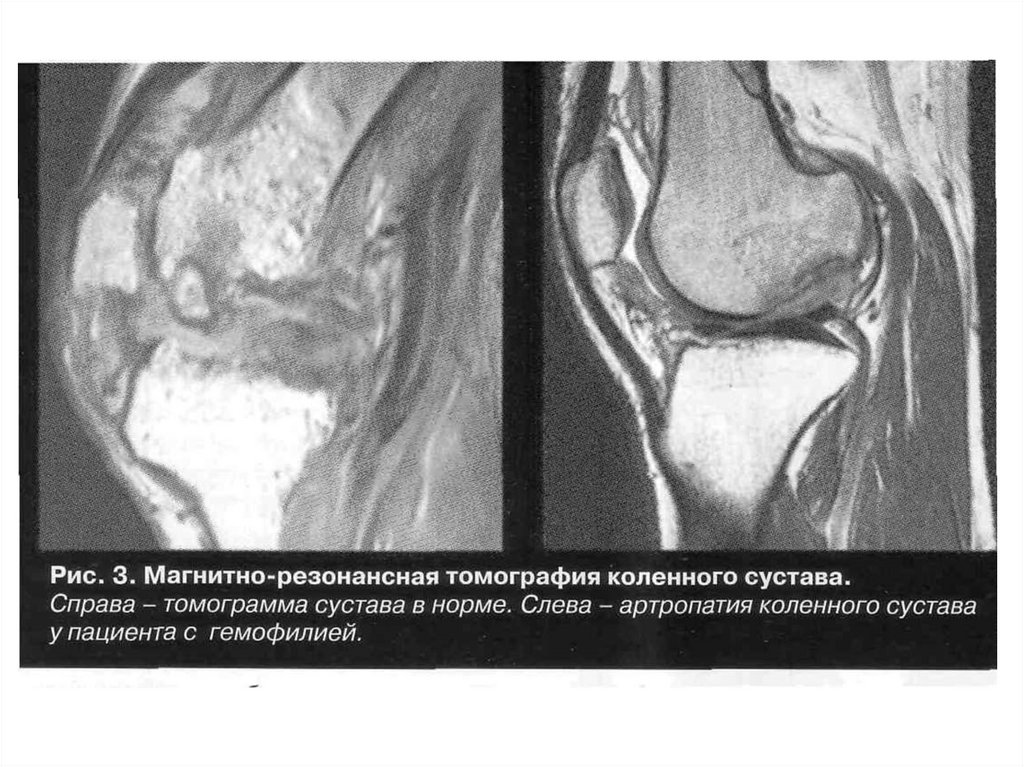

СПАСИБО ЗА ВНИМАНИЕ

52. Поражения суставов при гемофилии

• Гемартрозы, осложняющиеся острым и хроническим

синовитом, пропитыванием тканей гемосидерином,

остеоартрозы, ревматоидный артрит

• Поражение периартикулярных тканей с развитием

контрактур